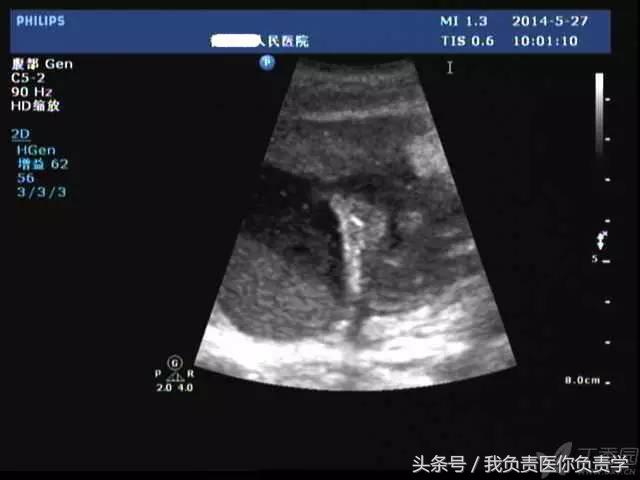

典型病例 4

患者女,79岁,晚餐后出现脐周疼痛数小时急诊。患者无发热,实验室检查示白细胞14×109/L,临床考虑阑尾炎,行超声检查所见如下:

图1示胆囊充盈差,囊壁明显增厚,胆囊周围可见无回声环绕分布